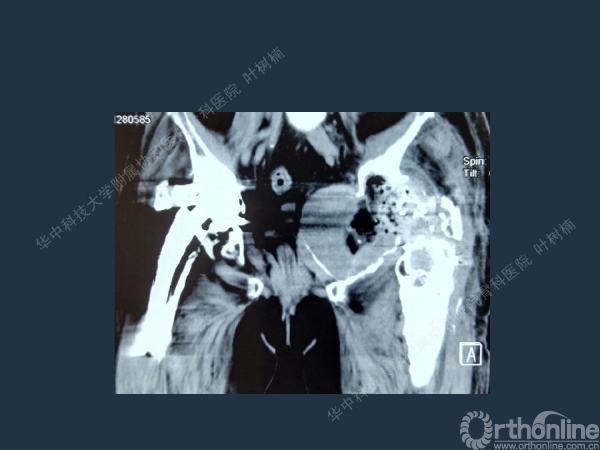

股骨侧翻修

髋臼缺损的处理